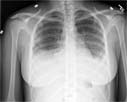

Posteroanterior chest on a normal female.